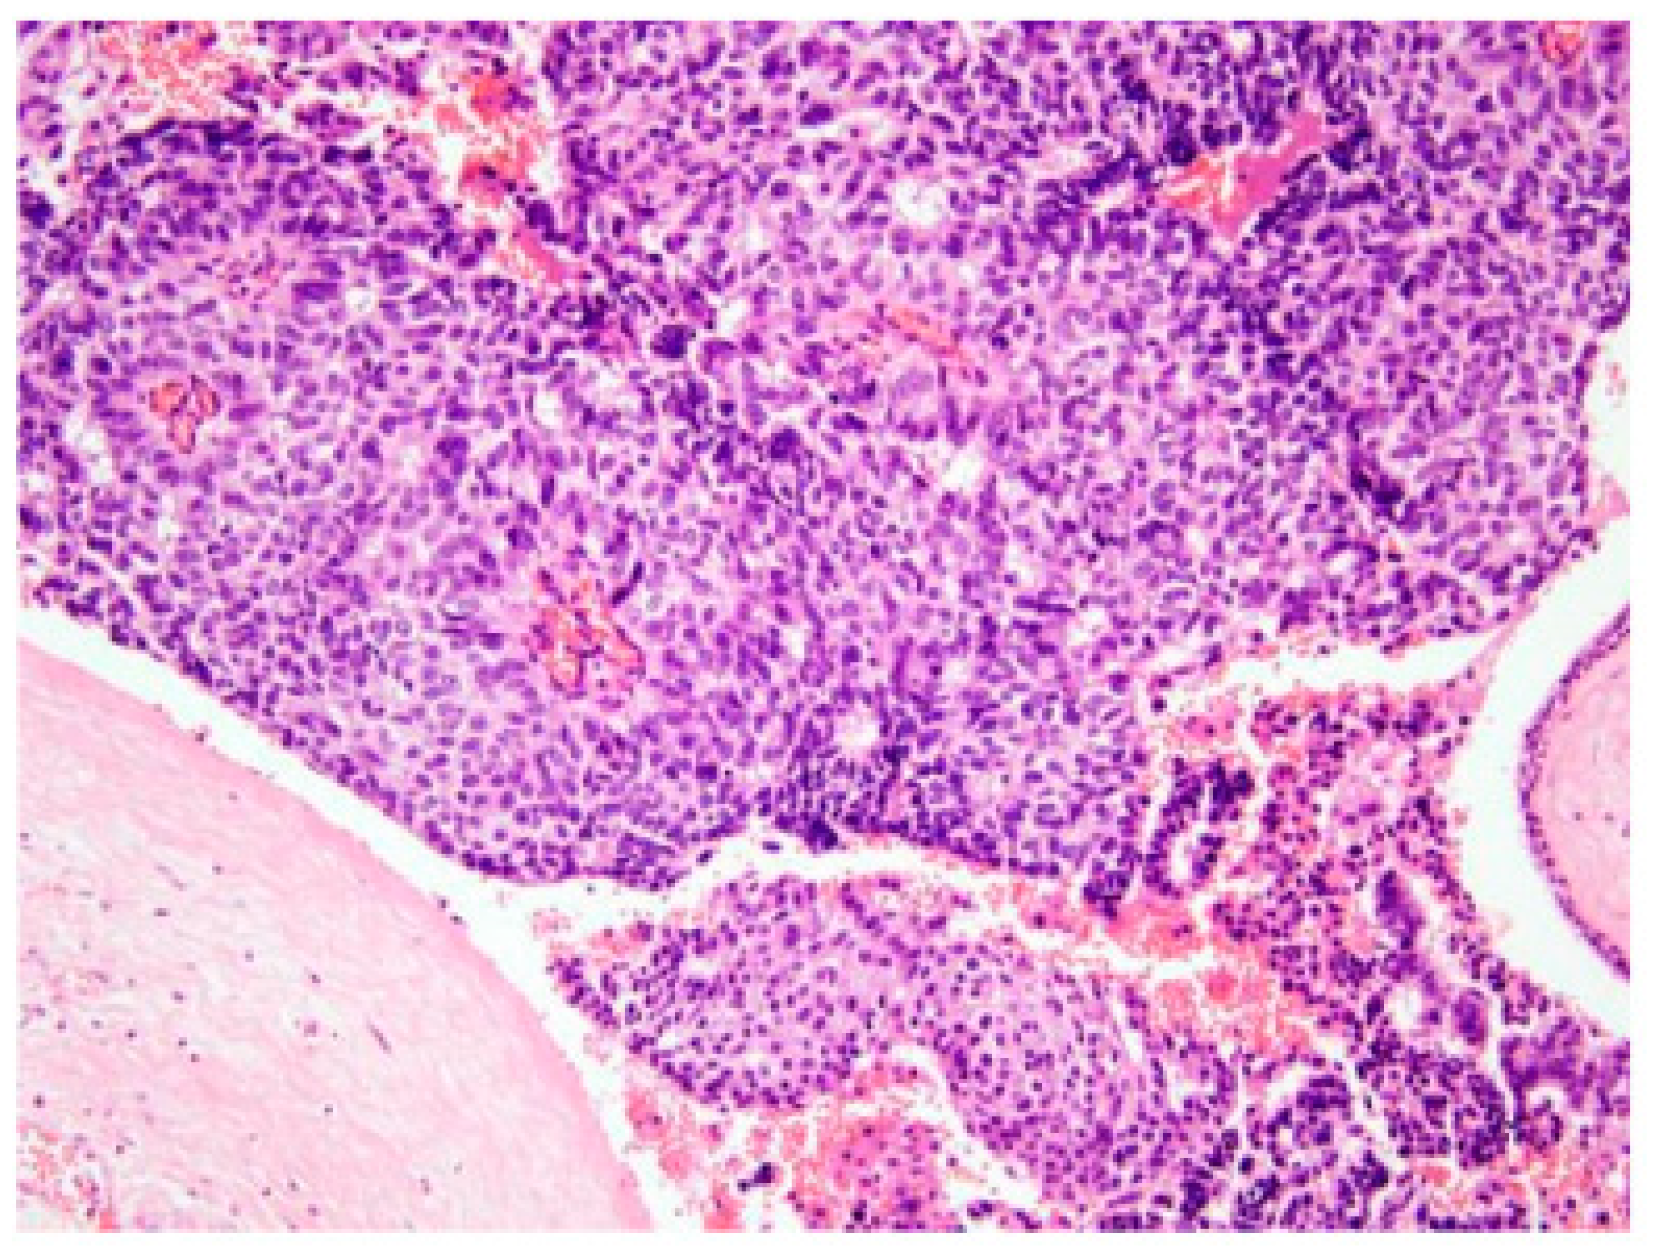

| Patchy erythematous duct irregularities | 2 (3.5) | Ductal carcinoma in situ (n = 2) |

| Papillary carcinoma and DCIS (low grade) | 1 |

| DCIS and microinvasion | 1 |